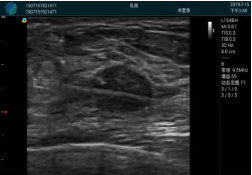

清晰顯示腺體內低回聲快影,邊界清晰,包膜較光滑

確定進(jìn)針路徑并實(shí)時(shí)監測抽吸針與腫塊位置關(guān)系

抽吸針進(jìn)入腫塊內部進(jìn)行旋切

抽吸過(guò)程中可見(jiàn)腫塊明顯縮小,并根據腫塊位置改變針道位置

抽吸旋切后再進(jìn)行超聲復查,原腫塊區域未見(jiàn)殘留組織及出血